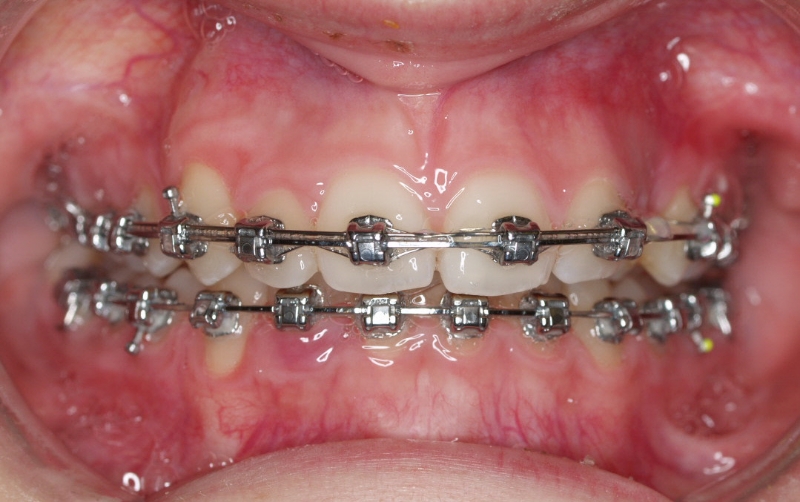

Clase II paciente 15 años

La paciente O.O. acude a nuestra consulta por:

– Canino 13 e incisivo lateral 42 en posición ectópica.

– Canino 23 incluido.

Con lo que decide realizarse un tratamiento de ortodoncia de duración de 24 meses con brackets damon Q.

CASO COMPLETO: